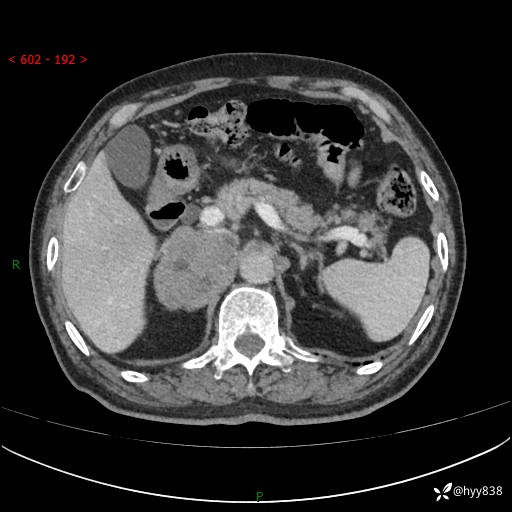

【患者信息】:76岁/男

【主诉】:检查发现右侧肾上腺占位6天

【现病史及既往史】:患者6天前体检发现右侧肾上腺占位,无腰痛,无放射痛,无尿频、尿急、尿痛及肉眼血尿,无畏寒、发热,无恶心、呕吐,今为求进一步治疗,遂来我院就诊,门诊拟“右侧肾上腺占位”收住入院。 起病以来,患者精神、饮食、睡眠可,大小便如常,体力体重无明显变化。

【检查】:肾上腺CT平扫+增强